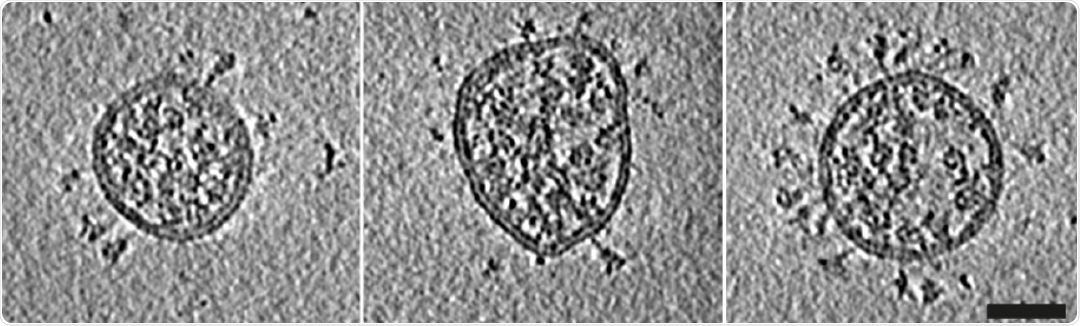

Characterization of virus production and representative images of intact, authentic SARSCoV-2 virions. (A) Western blot analysis of SARS-CoV-2 S and N in lysates of VeroE6 cells and in virus preparations. In released virions, S is present in both cleaved and uncleaved forms. (B) Four representative tomographic slices of SARS-CoV-2 virions from the supernatant of infected cells. Virions are approximately spherical, contain granular density corresponding to N-packaged genome, and have S protein trimers protruding at variable angles from their surfaces. Scale bar 50 nm. (C) Three example S trimers from the dataset shown as projections through the trimer to illustrate the variable tilt towards the membrane. Scale bar 10 nm.

Central slices through representative viruses. Virions from Calu-3 cells had a slightly broader diameter distribution than those from VeroE6 cells. Scale bar 50 nm.